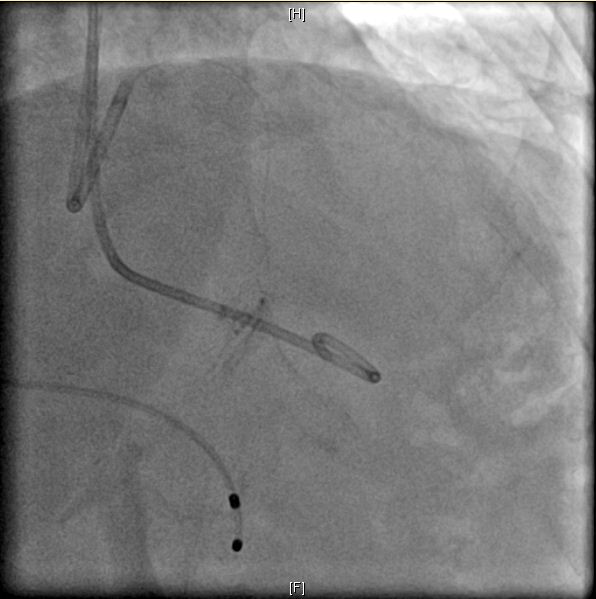

图: 冠状动脉第二间隔支S2粗大(左) 图: 造影示冠状动脉S2闭塞(右)